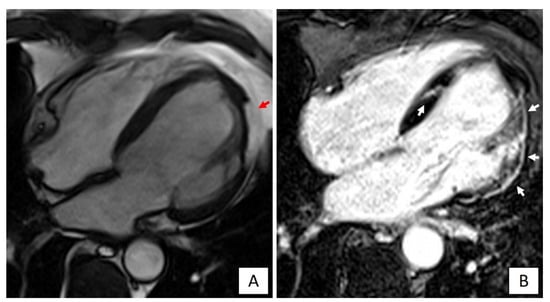

- RV morpho-functional abnormalities (segmental RV wall motion abnormalities plus RV dilatation or dysfunction) on imaging tests such as contrast echocardiography, CMR or cine-ventriculography [5]. The ECG features typically precede the morpho-functional abnormalities, becoming more extensive with the progression of the disease. Interestingly, a higher RV dilatation and lower RV ejection fraction are associated with the extent of TWI toward left precordial and inferior leads, and prolonged TAD [60].

3.3.2. Biventricular or Left Dominant Variants